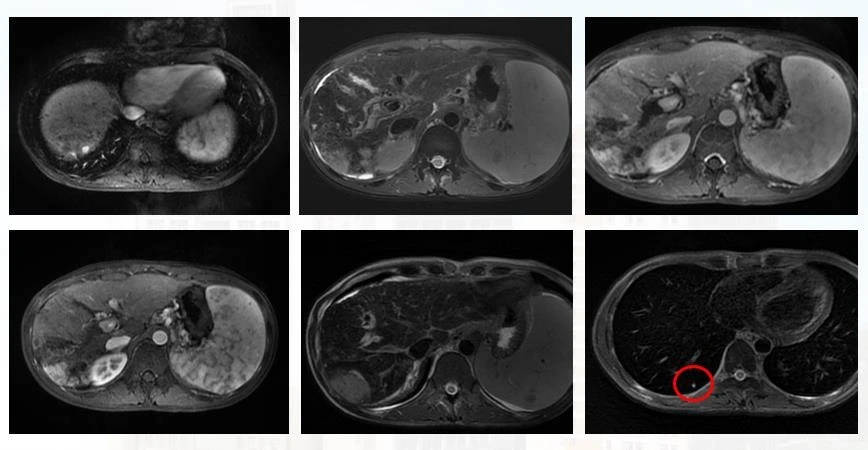

第四个疗程后复查CT( 2020-08-4,见上图 ),肝内肿物较前明显缩小、减少,门脉癌栓范围较前缩小,肺内病灶较前进一步缩小。

患者入院时胆红素为81.3umol/L,治疗一次后尽管升至99.7umol/L,但继续动脉灌注化疗后持续下降,最近复查降至25.6umol/L,患者的症状较前明显好转。